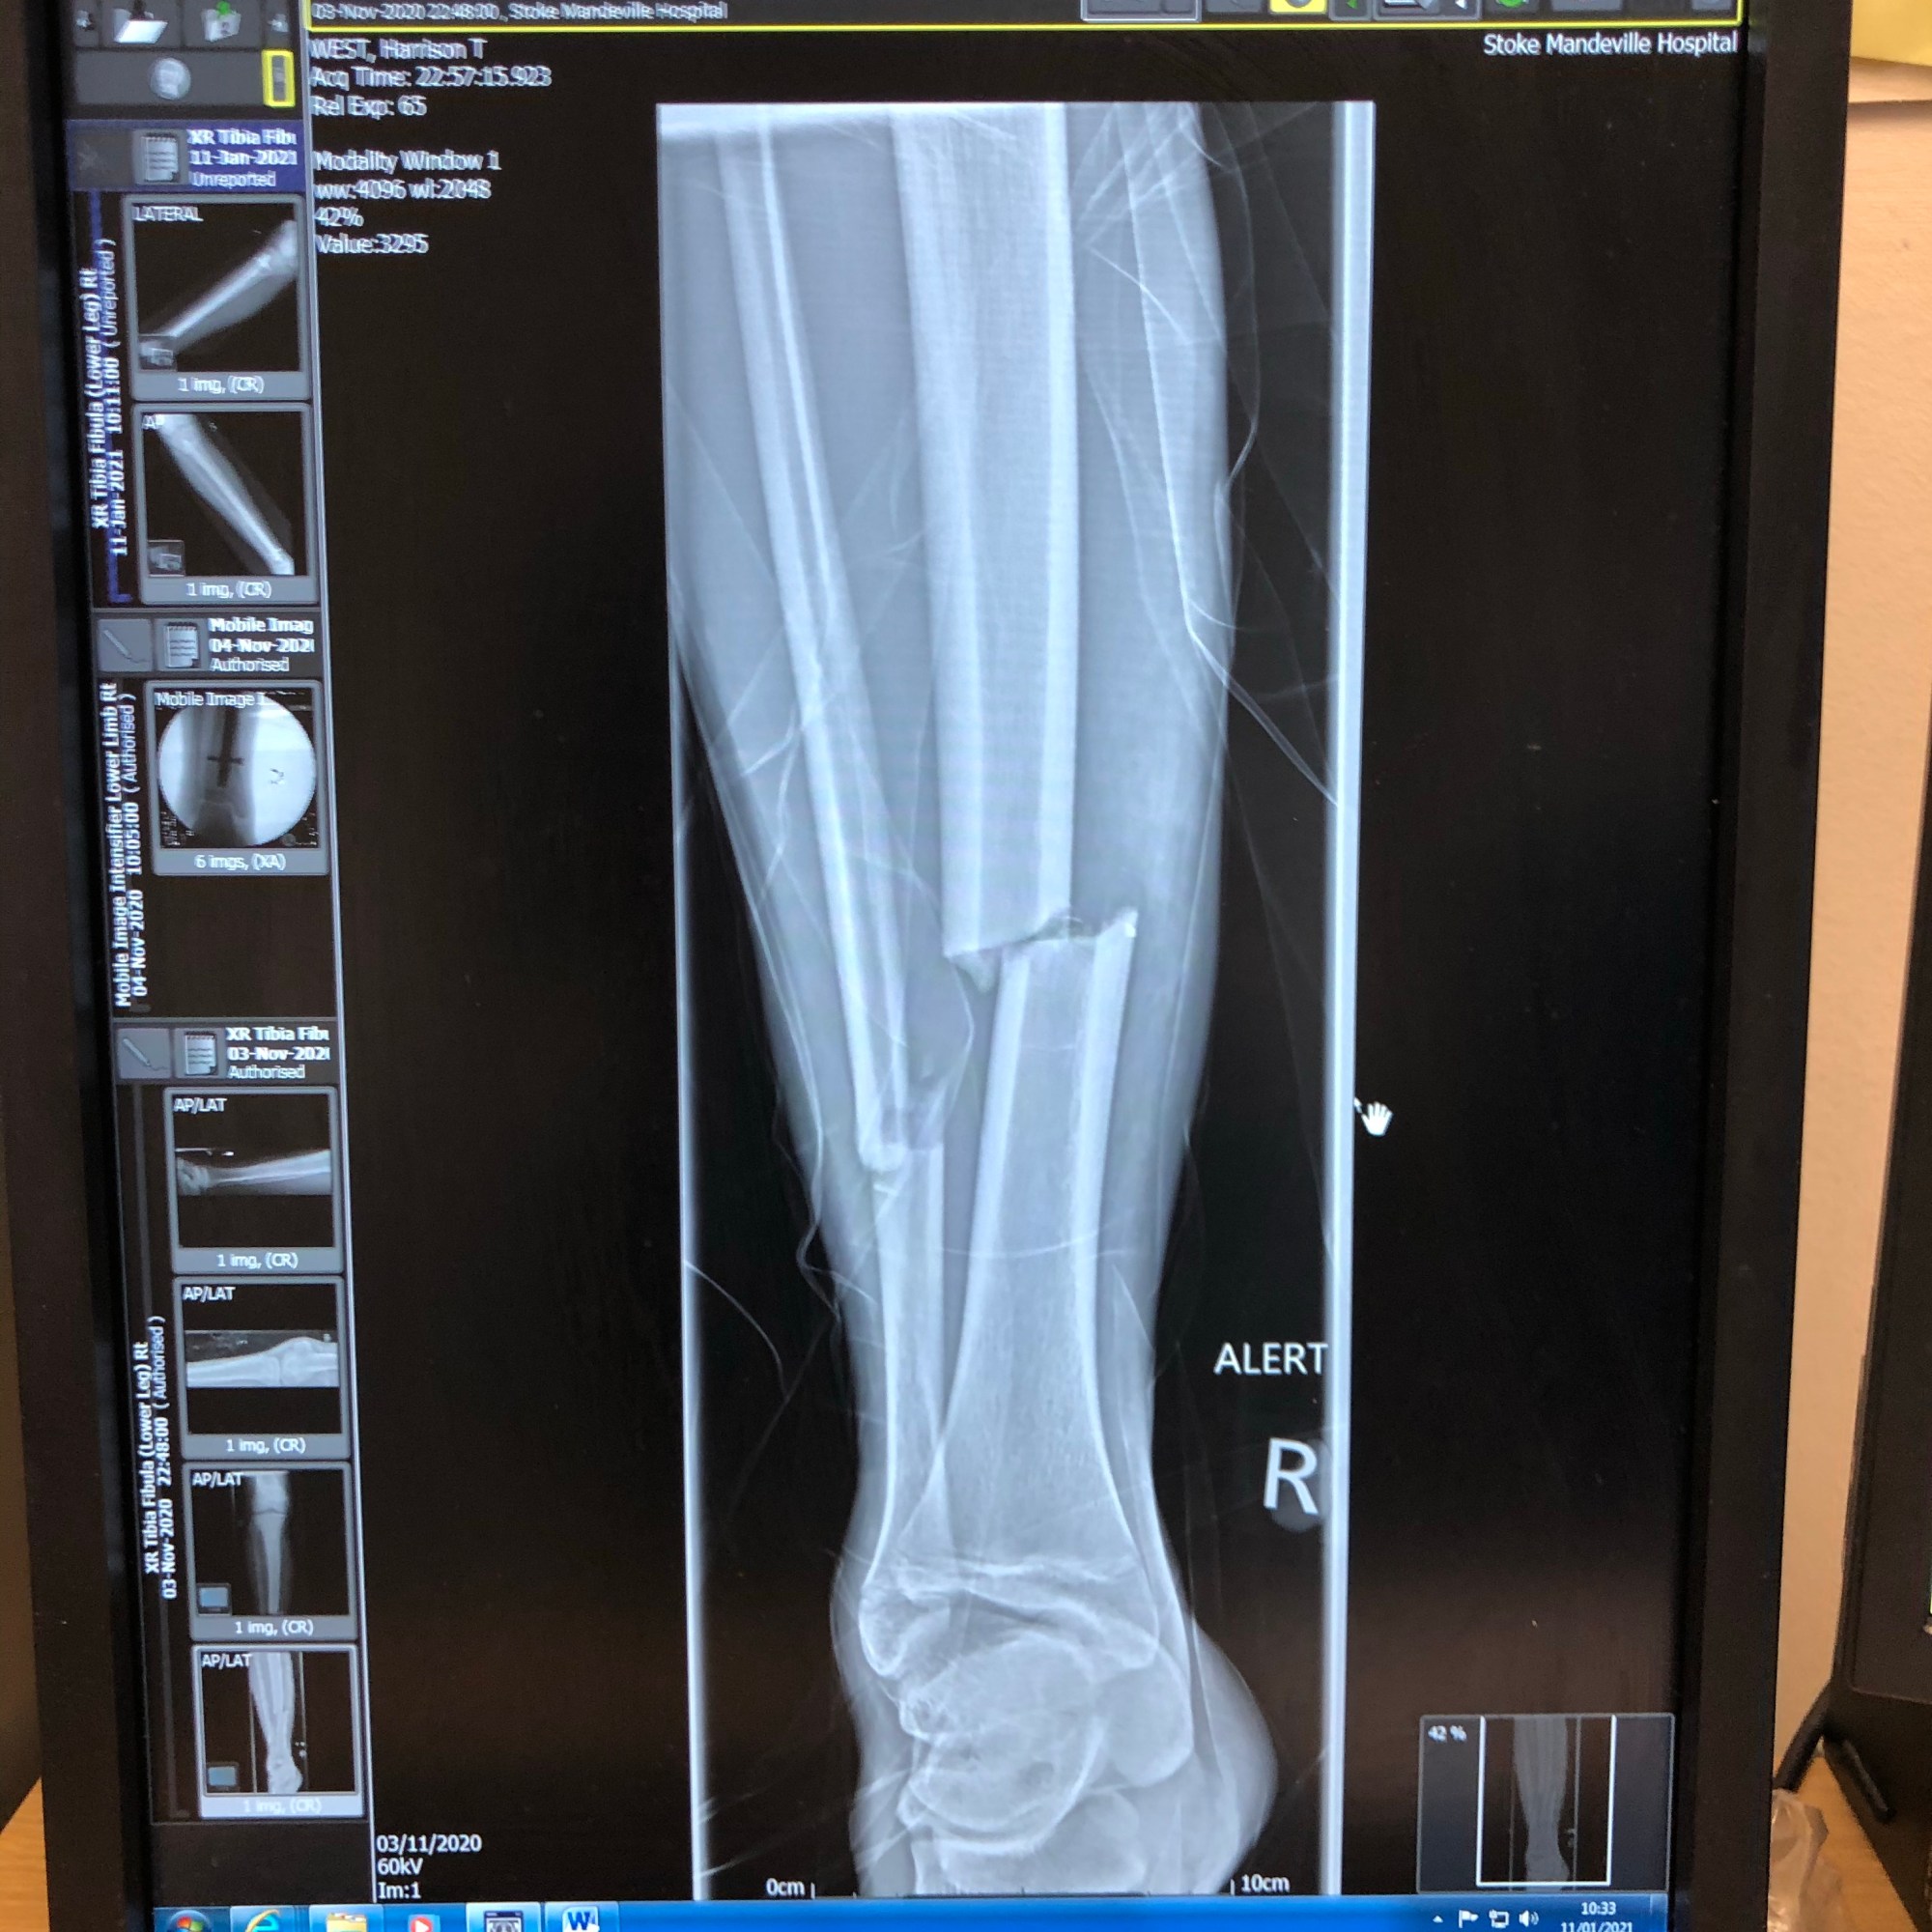

On a personal note this year has been brought much drama, We have had 3 broken bones, a collarbone in August and both Fibula and Tibia broken in November resulting in surgery with a nail inserted through H’s right leg. The road to full recovery will be long, both physically and mentally but ‘H’ is one tough cookie and I have witnessed an inner steel in him that will stand him in great stead for the future, literally !